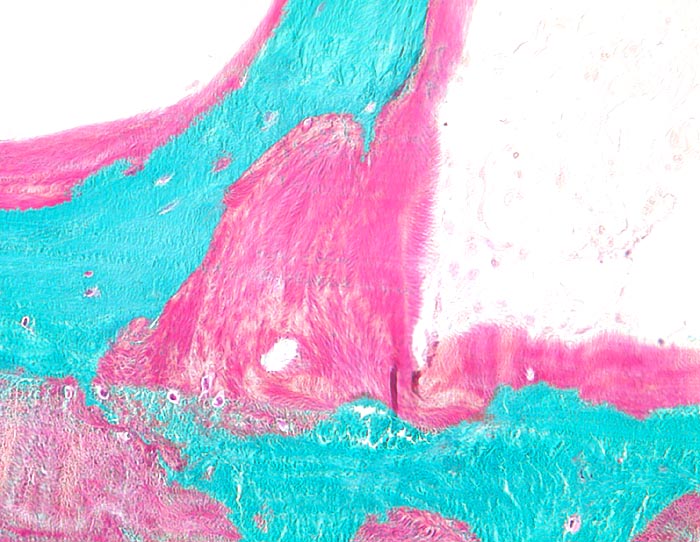

Morphologische Merkmale (Goldner Färbung):

• Verbreiterte unmineralisierte Osteoidsäume (rot).

• Reduzierte Menge von mineralisiertem spongiösem und kortikalem Knochen (grün).

• Schmale, rarefizierte und nur geringgradig vernetzte Knochenbälkchen bei Osteoporose.